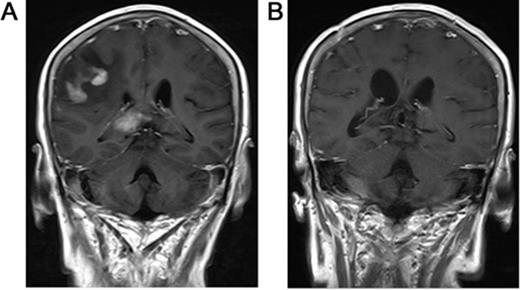

Kaplan-Meier curve shows clinical prognostic variables and their relationship to OS and/or PFS.